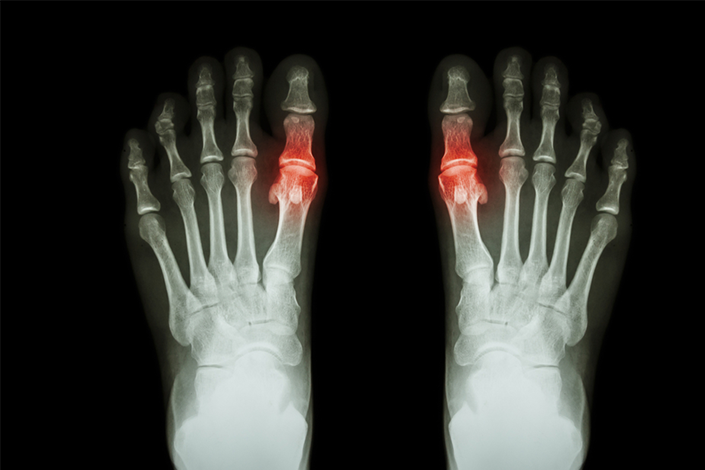

Dna moczanowa jest przewlekłą chorobą związaną z odkładaniem się kryształów moczanu sodu w stawach i innych tkankach. Jest najczęstszą postacią zapalenia stawów, dotyczy ok. 1–3% dorosłej populacji w krajach rozwiniętych, częściej chorują mężczyźni (1), a chorobowość wzrasta wraz z wiekiem.

Zdjęcie: Photogenica